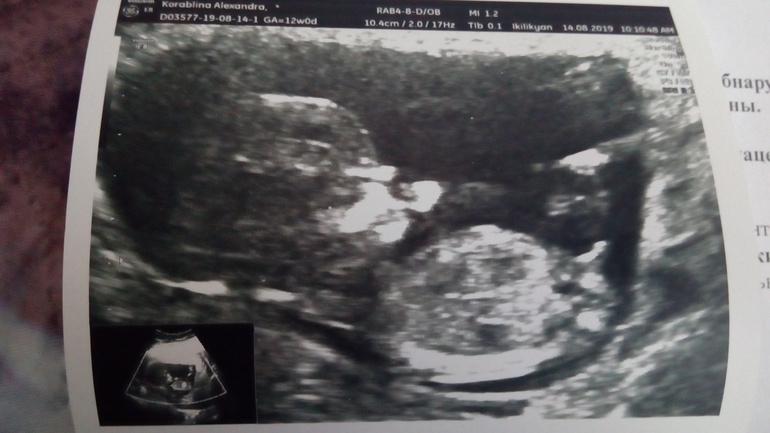

Похож на мальчиковый бугорок)) сама сижу гадаю! Посмотрите кого видите у меня?))

У вас похоже девочка 😊 но я тоже не эксперт, только вот по такой картинке знаю можно определять) угол

На втором скрининге узнаем точно! Здоровья нашим деткам главное) а пол, не так важен)